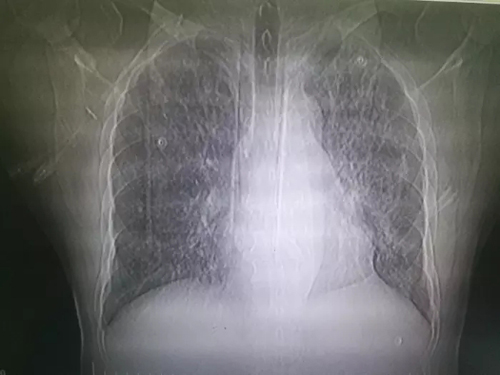

2018年12月22日,周六,正值冬至,当大家都阖家团圆,在家吃饺子的时候,重症医学科护士站突然响起一阵急促的电话铃声,“心内二科急会诊!”,电话里心内科护士简单的描述了患者的情况——男性,60岁,职业厨师,此次以“间断发热10天,加重伴心悸、胸闷2小时”主诉入院。入院时患者口唇发绀,氧和低,心率快,血压低,并很快出现意识不清,予以气管插管接呼吸机辅助通气,血管活性药物升压等治疗,目前患者血压维持尚可,但吸纯氧条件下氧和无任何改善。接到消息,我科二线医师杨改宁立即前往会诊,随后通知值班医师张维纳(笔者本人)带着转运呼吸机赶去心内二科重症监护室快速将患者接回重症医学科。转入时患者呼吸费力,血氧饱和度只有75%(呼吸机控制通气,氧浓度100%)。科主任李鹤云再次详细向家属追问病史,分析病情后考虑肺部感染,呼吸衰竭,ARDS诊断成立,但不排除流感。立即给予积极抗感染、升压、改善循环,上调呼吸机参数等治疗,行咽拭子、血培养、痰培养等病原学检查。同时紧急予以单间负压病房隔离及标准预防,护士长牛辉妮立即为患者使用密闭式吸痰管。患者氧和稍有改善后由主管医生张维纳和当班管床护士段静陪同外出行胸部CT检查,结果提示严重肺部感染,左肺几乎完全实变。